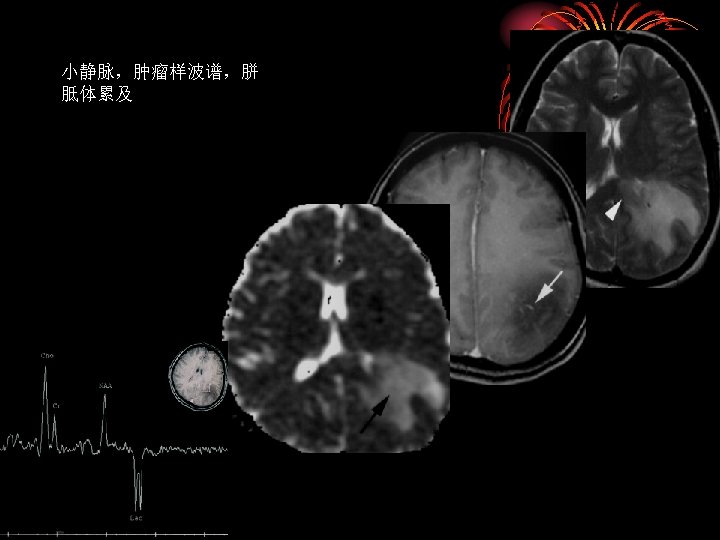

• TDLs非闭合性增强是鉴别诊断的依据之 一;非脱鞘病(炎症、肿瘤等)只有7%出 现非闭合性环形增强 • TDLs水肿程度及占位效应相对较轻 Distinguishing Tumefactive Demyelinating Lesions from Glioma or Central Nervous System Lymphoma: Added Value of Unenhanced CT Compared with Conventional Contrast-enhanced MR Imaging Radiology 2009, 251(2): 467 -484